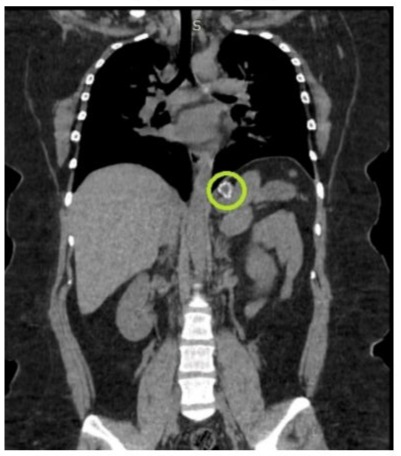

The surgical procedure performed included: (1) careful detumorization to separate adhesions, (2) total splenectomy due to the size of the cyst and the involvement of the splenic parenchyma, (3) placement of two biobag-type drains in the tumor bed and in the pelvic cavity, and (4) prophylactic appendectomy. The surgery was classified as R1 (resection with positive microscopic margins). Intraoperative bleeding was significant, reaching 2400 cc, which required intensive hemodynamic management. The patient was admitted to the ICU immediately after surgery. Close monitoring of hemodynamic parameters was performed, and postoperative anemia was managed. Histopathology confirmed giant splenic cysts with a collagenous wall and reactive epithelial lining. Hematopoietic collection and coagulative necrosis were observed in the adjacent parenchyma. The appendix presented acute peritonitis. Hematological controls two weeks after surgery showed persistent anemia (Hb 10.5 g/dL) and reactive thrombocytosis (630,000 platelets/mm³), common after splenectomy. Twenty days after surgery, a follow-up CT scan was performed, which showed the absence of a spleen with free fluid and inflammatory changes in the surgical bed, persistence of pleural effusion, a probable residual cyst in the gastric fundus measuring 33x58 mm, and retroperitoneal lymphadenopathy (up to 17 mm). After this consultation, follow-up was continued, and at 6 months, a new CT scan showed resolution of the inflammatory changes and lymphadenopathy, as well as the absence of a residual cyst. The patient was referred for an appropriate vaccination regimen against encapsulated organisms (Figure 1).

Figure 3: Total splenectomy due to the size of the spleen, the decision to perform a total splenectomy in this case was based on the exceptional size of the cyst (40x30 cm)

The decision to perform a total splenectomy in this case was based on the exceptional size of the cyst (40x30 cm) and its extensive involvement of the splenic parenchyma. Although the current trend favors spleen-sparing procedures, such as laparoscopic fenestration or partial splenectomy [12], the size of the cyst in this case justified a more radical approach. Mertens et al. (2007) reported good long-term results with total splenectomy for nonparasitic splenic cysts, with a recurrence rate of 0%, compared to 25% with conservative procedures [13]. However, it is important to consider the possible long-term complications of splenectomy, especially in young patients. The significant intraoperative bleeding (2400 cc) observed in this case is common in surgeries for giant splenic cysts due to increased vascularity and adhesions. Madhok et al. (2014) emphasize the importance of careful hemostasis and the possibility of requiring blood transfusions in these cases [14]. Postoperative anemia and reactive thrombocytosis observed in hematological controls are expected findings after splenectomy. Di Sabatino et al. (2011) described post-splenectomy thrombocytosis as a common phenomenon that usually resolves within 6-12 months [15]. However, it is crucial to monitor these parameters due to the increased risk of thromboembolic events in the early postoperative period.